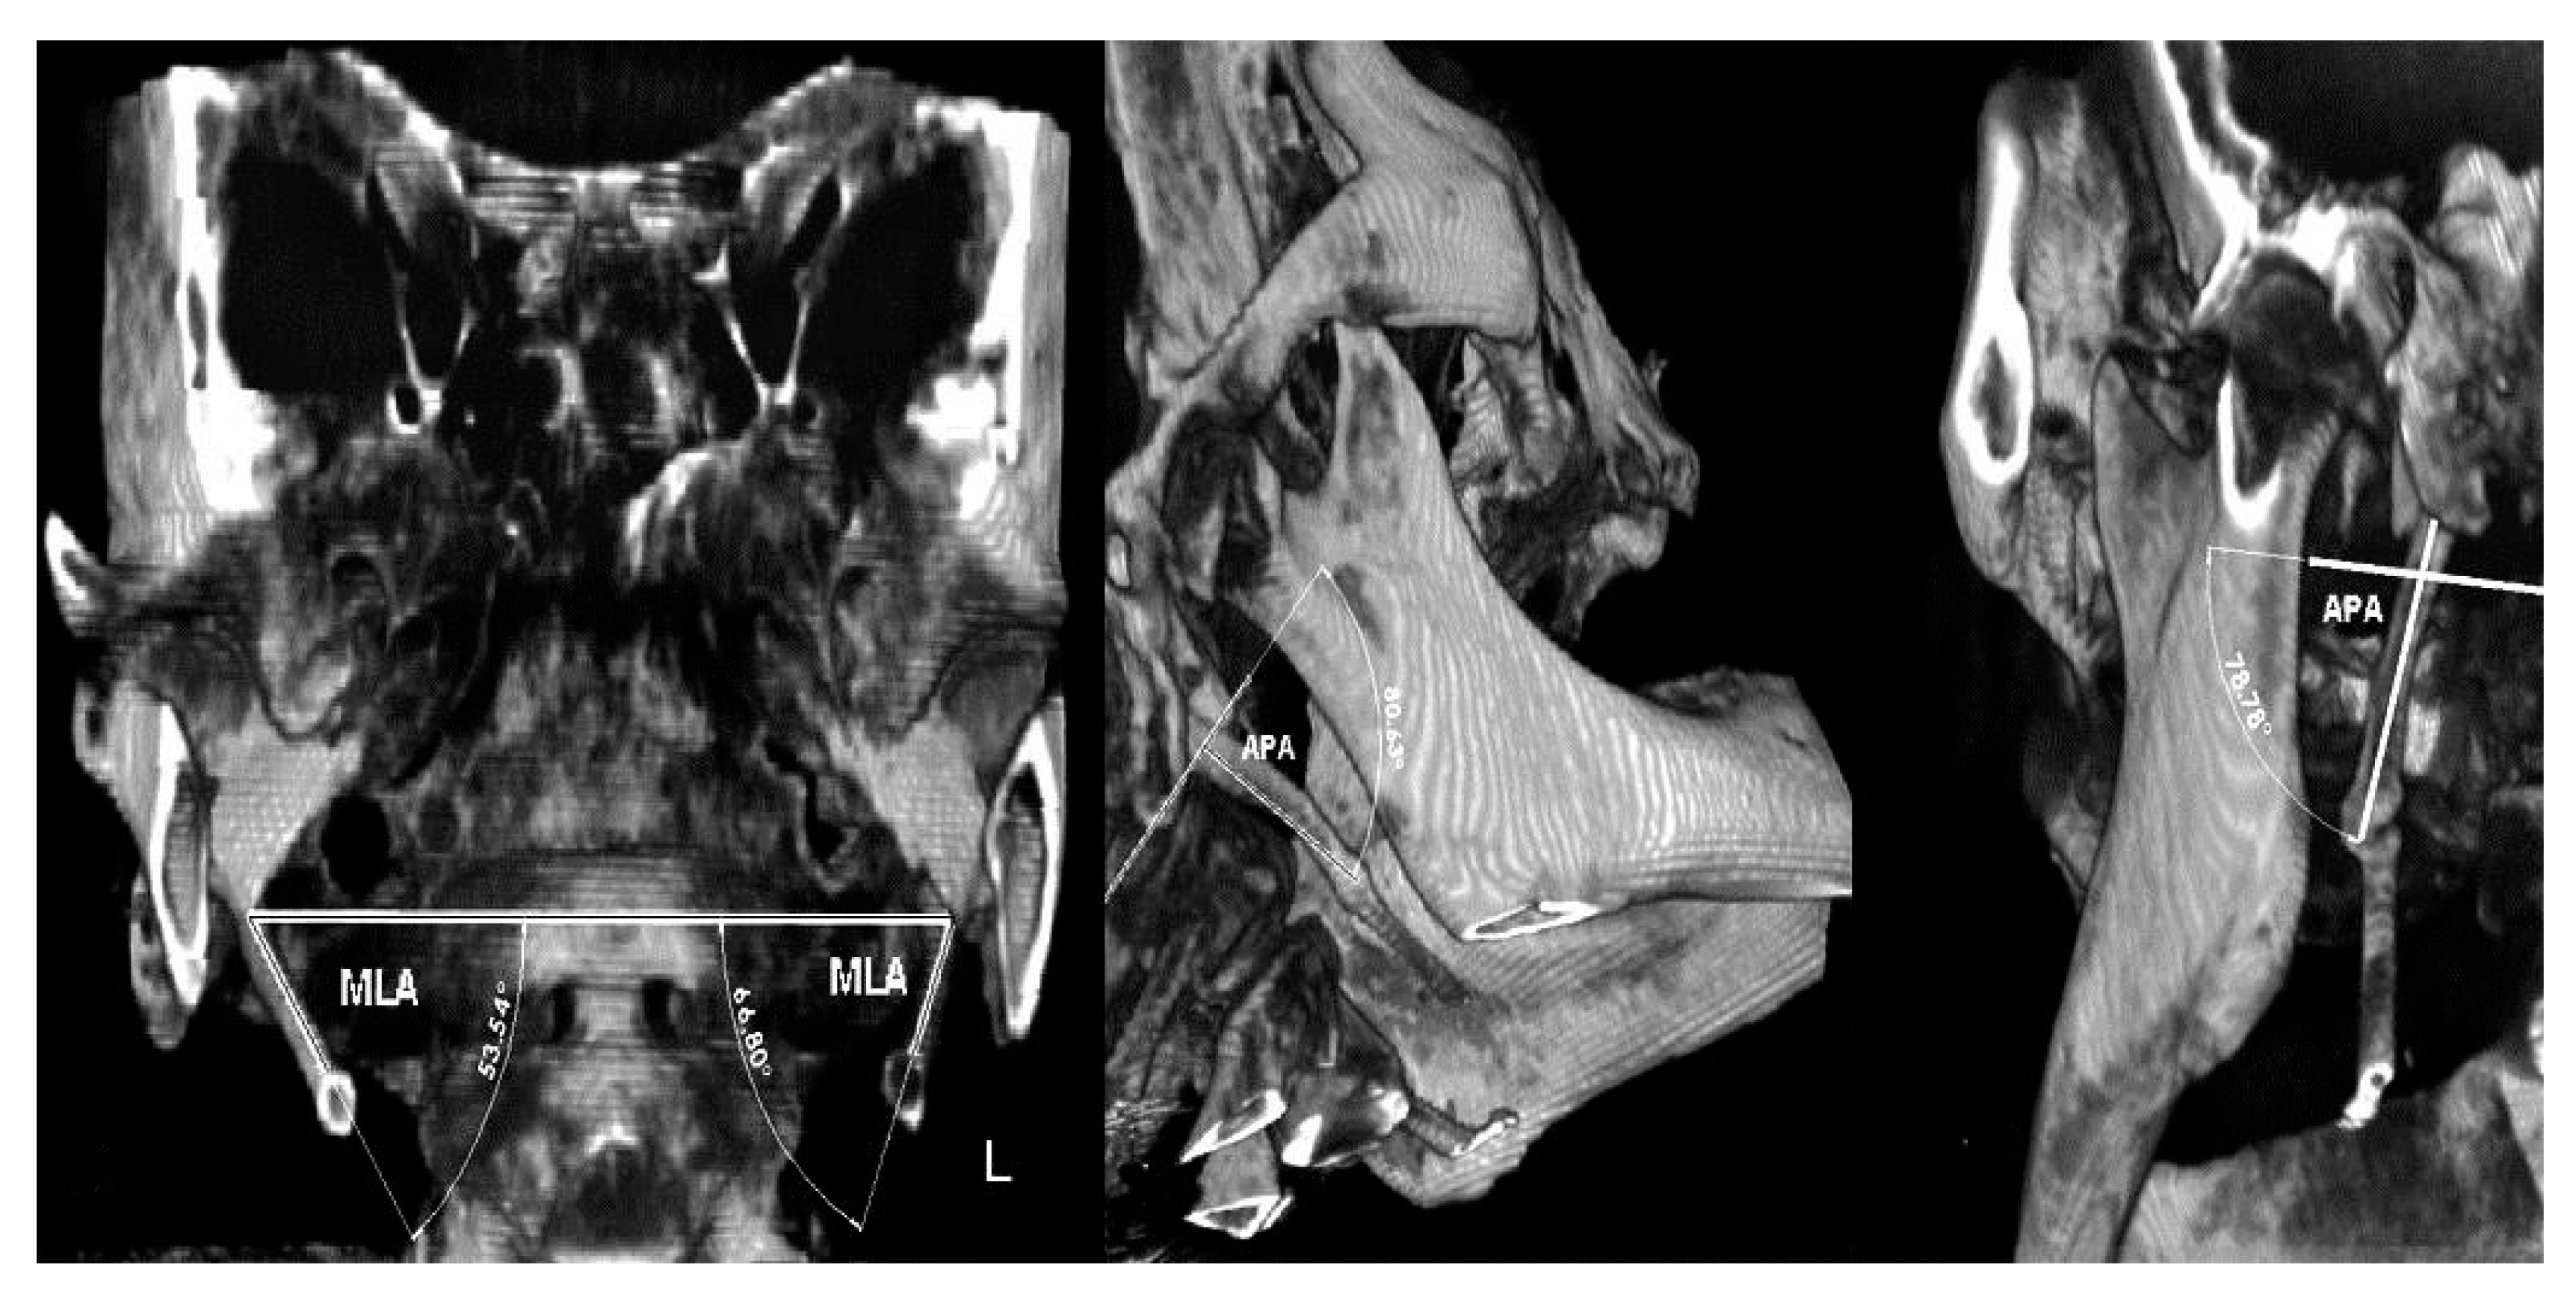

It is a rare condition caused by an elongated or disfigured styloid process which interferes with the functioning of neighboring structures and gives rise to orofacial and cervical pain often triggered by neck movements. I have great insurance so I paid very little of that total although my insurance only paid about half of the total. We report two patients with cerebrovascular symptoms of Eagle syndrome treated in our medical center in the past year.

For language access assistance contact the NCATS Public Information Officer. This procedure called a styloidectomy can be done through the mouth or neck. He first published his data in 1937 with a series of 200 patients presenting with. I think the total for my surgery was 20000-21000. A 47-year-old man present with lump sensation in his left-side throat for few months after UPPP an operation for snoring. The patient became symptom-free at 9 months after the surgery. Surgery to shorten the styloid process is the primary treatment for Eagle syndrome. BACKGROUND Eagle syndrome is an unusual condition in which the styloid process SP becomes elongated and causes different clinical symptoms due to pressure on adjacent anatomical structures. My surgery was billed as a mini-craniectomy.